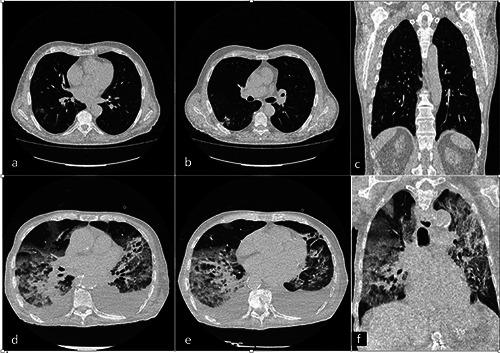

Of the 218 patients, 23 (20 males: 3 females; mean age 60 years) required ICU admission, 195 (118 males: 77 females, mean age 64 years) were admitted to a clinical ward. Compared with non-ICU patients, ICU patients were predominantly males (60% versus 83% p=0.03), had more comorbidities, a positive CRP (p=0.04) and higher LDH values (p=0.008). ICU patients' chest CT demonstrated higher incidence of consolidation (p=0.03), mixed lesions (p=0.01), bilateral opacities (p<0.01) and overall greater lung involvement by consolidation (p=0.02) and GGO (p=0.001).

在218例患者中,23例(男性20例:女性3例;平均年龄60岁)需要入住ICU,195例(男性118例:女性77例,平均年龄64岁)入住临床病房。与非ICU患者相比,ICU患者以男性为主(60%对83%,p=0.03),合并症更多,C反应蛋白(CRP)阳性(p=0.04),乳酸脱氢酶(LDH)值更高(p=0.008)。ICU患者的胸部CT显示实变发生率更高(p=0.03)、混合性病变(p=0.01)、双侧混浊(p<0.01),总体上实变(p=0.02)和磨玻璃影(GGO)(p=0.001)累及的肺组织更多。